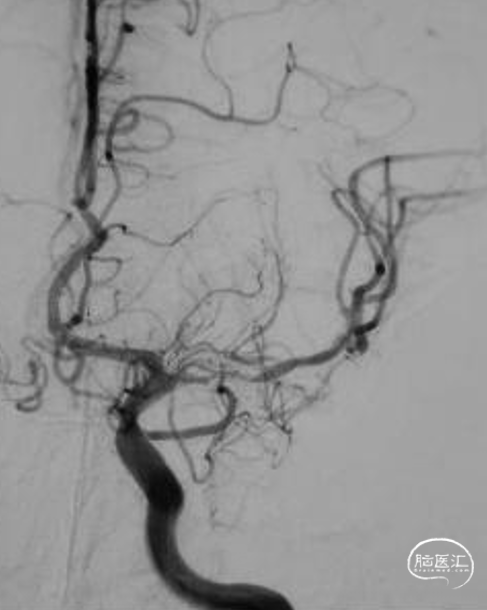

➢脑血管DSA

➢RCCA

➢LCCA

释放自膨式闭环支架 4*16mm后造影。

最后正侧位造影。

正位

侧位